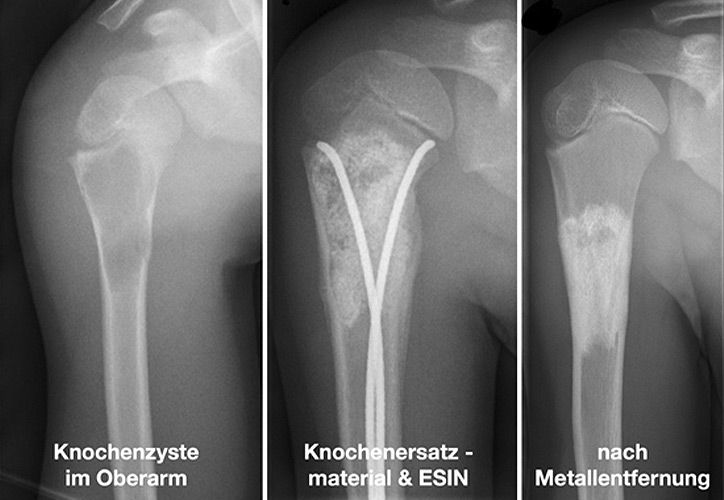

Knochenzysten sind die häufigsten gutartigen tumorähnlichen Knochenläsionen im Kindes- und Jugendalter und machen in großen Sammelstatistiken 13-19% dieser Läsionen aus. Es werden die juvenilen und aneurysmatischen Knochenzysten unterschieden. Der Altersgipfel für die meist zufällige Erstdiagnose liegt zwischen dem 9. und 13. Lebensjahr. Die Lokalisation der Knochenzyste verteilt sich nach Literaturangaben auf den Oberarm (ca 50%), den Oberschenkel (ca 30%), den Unterschenkel (ca 10%), aber sie können an allen Knochen vorkommen. Die genaue Pathogenese ist unklar, es werden jedoch lokale Wachstumsstörungen in der Entstehungsphase des Röhrenknochens diskutiert.

Um pathologische Frakturen zu verhindern, stehen mehrere Möglichkeiten zur Verfügung, z.B.:

• chirurgische Entfernung (a.G. der Größe meist nicht möglich)

• Stabilisierung und gleichzeitige Therapie durch ESIN (Nagelung)

• Auffüllung mit Knochenersatzmaterial oder körpereigenem Knochen

• Kombinationstherapie mit Knochenersatzmaterial und ESIN (Abbildung)